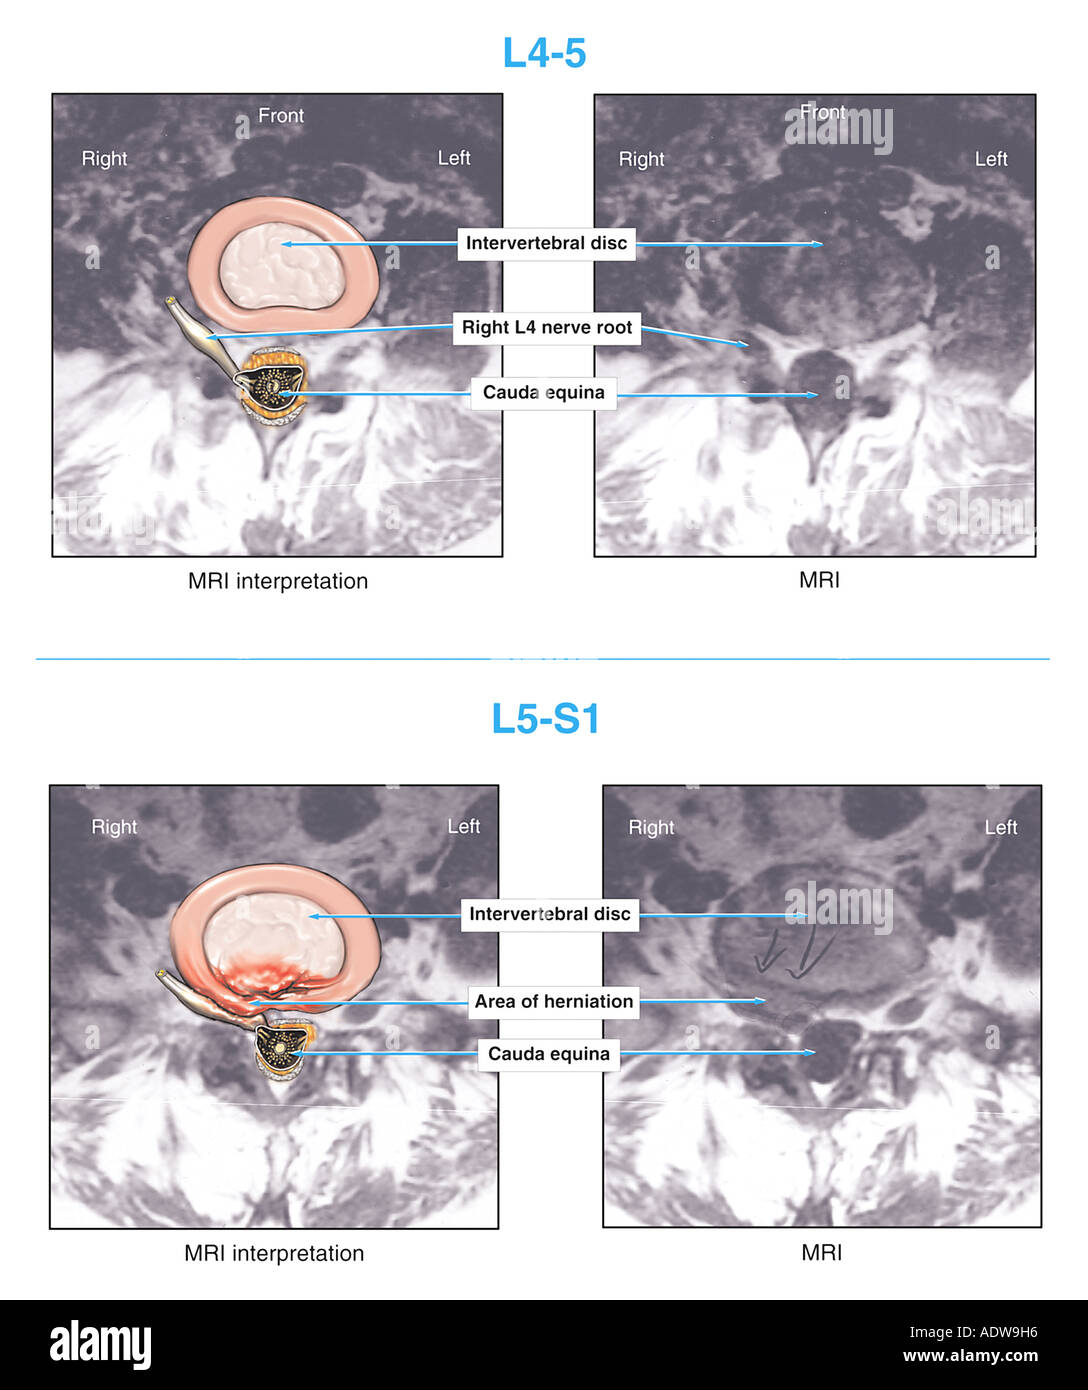

WebUna vez constatadas las restricciones y secuelas que hayan quedado al trabajador que haya sufrido una artrodesis lumbar, el siguiente paso para estudiar la. Web"Artrosis interfacetaria e hipertrofia de facetas en L4-L5 y L5-S1, hallazgo que puede justificar un síndrome facetario crónico.Discopatía y hernia extruida posterior en. WebPara los pacientes con las siguientes afecciones, si el movimiento anormal y excesivo en un segmento vertebral produce dolor intenso e incapacidad para funcionar, puede. WebPinzamiento del nervio S1 (en el nivel L5–S1): pérdida del reflejo del tobillo e imposibilidad de elevar los dedos de los pies, entumecimiento y dolor que puede irradiarse hasta la. WebEl proceso de recuperación de una artrodesis lumbar es lento y puede superar los 6 meses en muchos casos. La hospitalización tras la intervención es de unos. WebRiesgos de la artrodesis lumbar. Aparte de los riesgos que están asociados a cualquier procedimiento quirúrgico como lo son el sangrado excesivo, infecciones,. WebRM realizadas indicaron protusiones-hernias en L4-L5,L5-S1,y la última mostró discartrosis moderada con protusion posterocentral moderada y compromiso.

WebRM realizadas indicaron protusiones-hernias en L4-L5,L5-S1,y la última mostró discartrosis moderada con protusion posterocentral moderada y compromiso. WebEsto nos hace ver que la artrodesis vertebral solo se realiza en los casos más graves, siendo muy probable que antes de la operación hayamos padecido una serie de dolores.